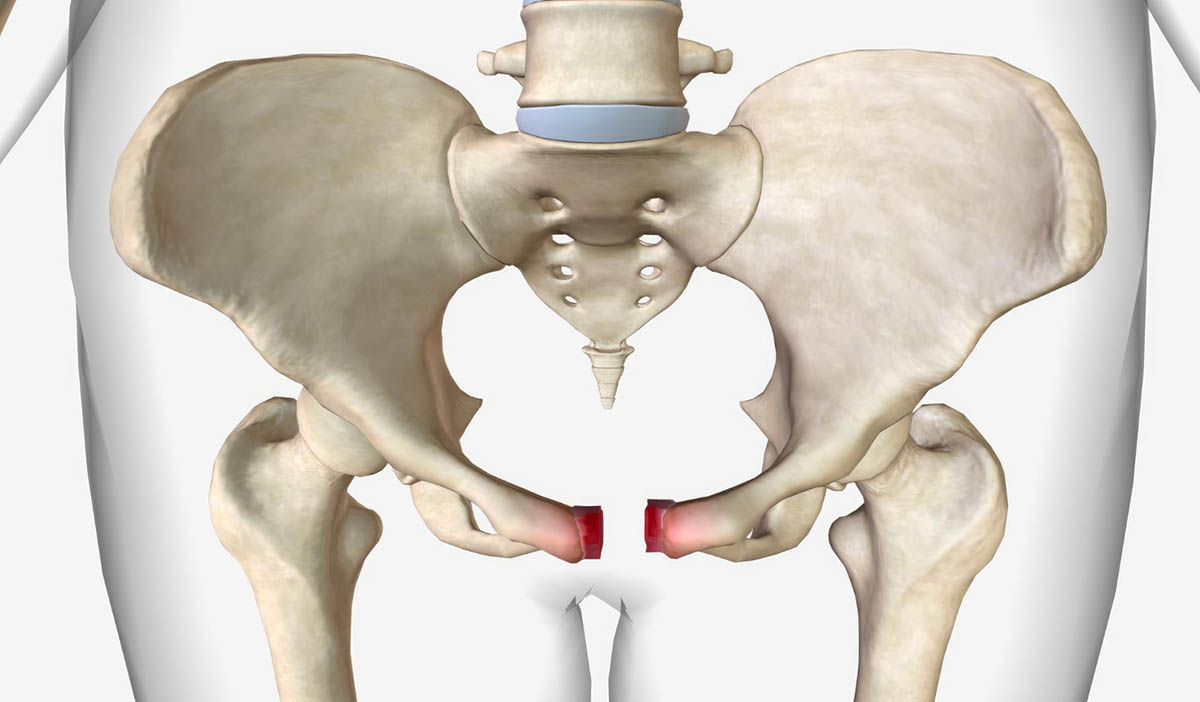

Pelvic & Complex Fractures

High-impact injuries requiring specialized management.